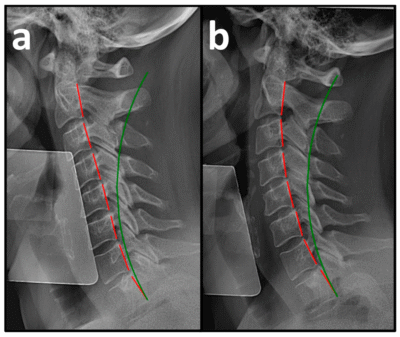

In “Improvement in Cervical Spinal Alignment and Posture May Redefine Recovery Pathways for Motor Vehicle Collision Whiplash Injury,” researchers report on 51 consecutive patients with moderate-to-severe neck pain and disability following motor vehicle collisions — all of whom had plateaued after 3–4 months of prior conservative treatment.

- Marked loss of cervical lordosis

- Significant anterior head translation

- Cervical lordosis improved by more than 12°

- Anterior head translation reduced by more than 12 mm

The authors also report strong correlations between improved cervical alignment (lordosis and anterior head translation measures) and reductions in both pain and disability.

This study is worth reading. It presents objective radiographic changes alongside major improvements in patient-reported pain and disability — in a population widely considered at high risk for chronicity.